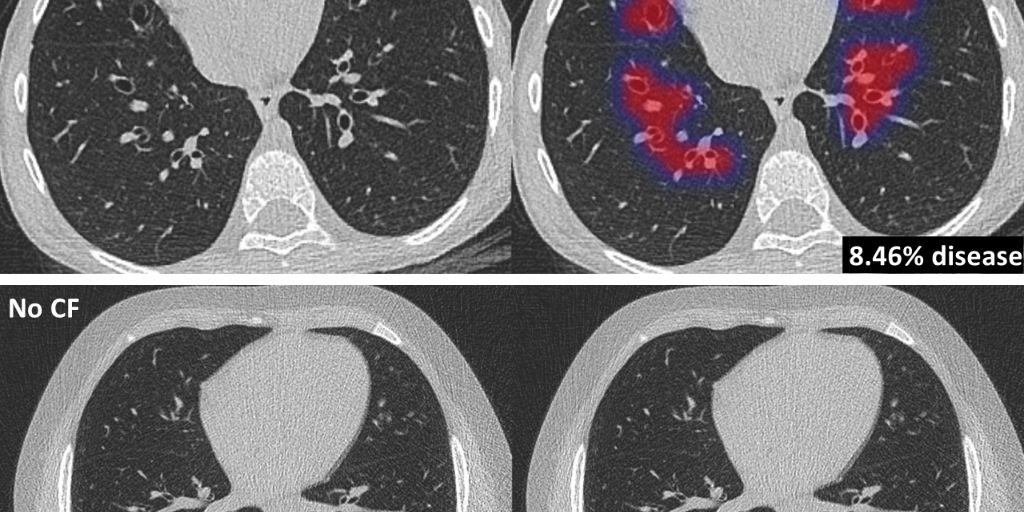

Thirona, an artificial intelligence (AI) software company specialising in medical image analysis, developed an AI algorithm that revolutionizes cystic fibrosis (CF) care. The new algorithm, coined PRAGMA-AI, allows for fast, automated analysis of CT scans of patients with CF to detect and quantify lung abnormalities related to CF. These quantifications are critical in determining the status of the patient and determine optimal treatment paths but are not feasible to be performed by humans in clinical care. The release of PRAGMA-AI paves the way for large-scale usage in clinical trials and clinical care for better diagnostics, patient monitoring, and treatment planning.

The new AI-based algorithm PRAGMA-AI, part of Thirona’s lung quantification software package LungQ, automatically identifies lung abnormalities related to CF, such as abnormal airways and collapsed lung tissue. These measurements supply sensitive and objective information on the pattern and extent of CF lung disease. This is critical information, allowing clinicians to monitor disease progression and supporting clinical decision-making for treatment plans. LungQ PRAGMA-AI has been validated on a large number of scans of CF patients, showing high diagnostic performance comparable to trained human analysts.